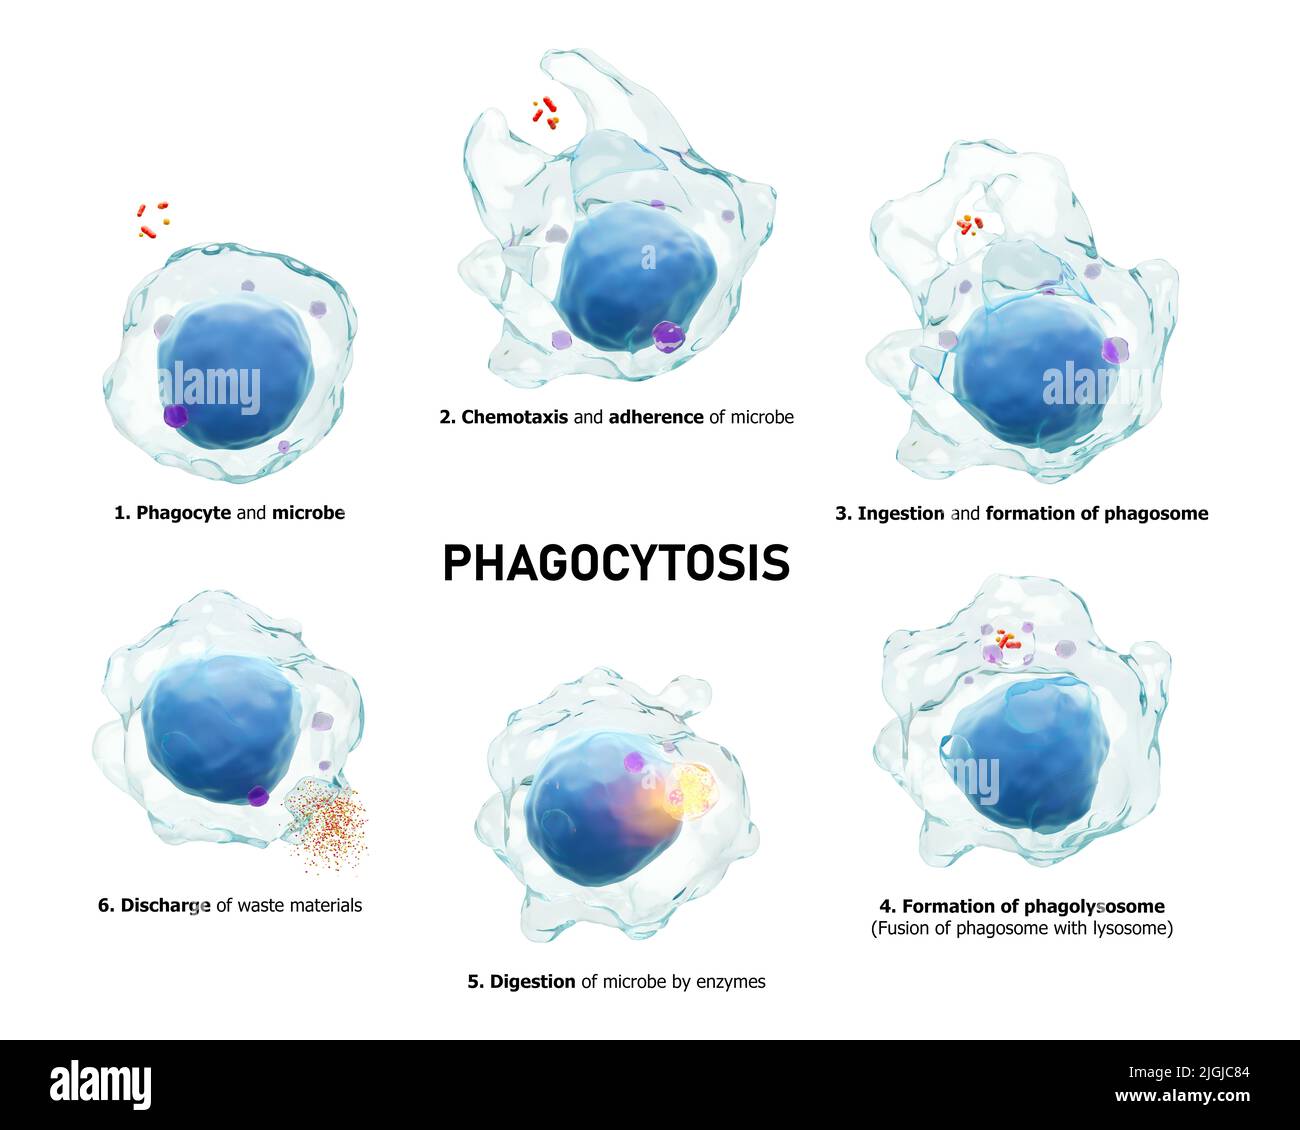

RF2JGJC84–Fagocitosi . Il processo graduale del macrofago è la deglutizione e l'uccisione di microbi. Fondo bianco isolato . Immunità medica concetto . 3D rende

RF2JGJC87–Fagocitosi . Il processo graduale del macrofago è la deglutizione e l'uccisione di microbi. Fondo bianco isolato . Immunità medica concetto . 3D rende